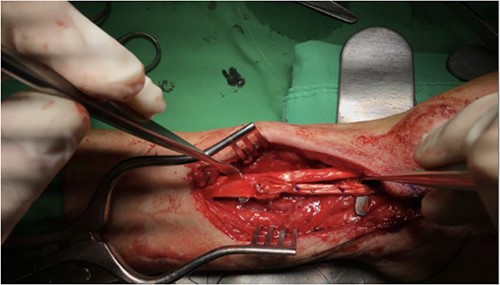

Pre-operative assessment was performed, and remove volar plate, tenolysis, release of flexor retinaculum and tendon graft reconstruction of FPL were performed on 1 November 2022, due to total severance with adhesion and fibrosis (Fig. 4). Post-operative pain control was given, and wound dressing was changed regularly. No fever or wound dehiscence was noted during her hospital stay. A rehabilitation specialist was consulted for a spica splint, and the Penrose drain was removed on 3 November 2022. She was discharged on 3 November 2022, in stable condition.

Post-operative photo showing removal of volar plate, tenolysis, release of flexor retinaculum and tendon graft reconstruction of FPL that were performed on 1 November 2022.

During the follow-up appointments at the rehabilitation OPD, which ended on 3 May 2023, the patient reported gradual improvement in her left thumb flexion and was satisfied with the outcome of the surgery. Physical examination revealed that the function of the second to fifth finger was not impaired, and there were no signs of infection or wound complications.